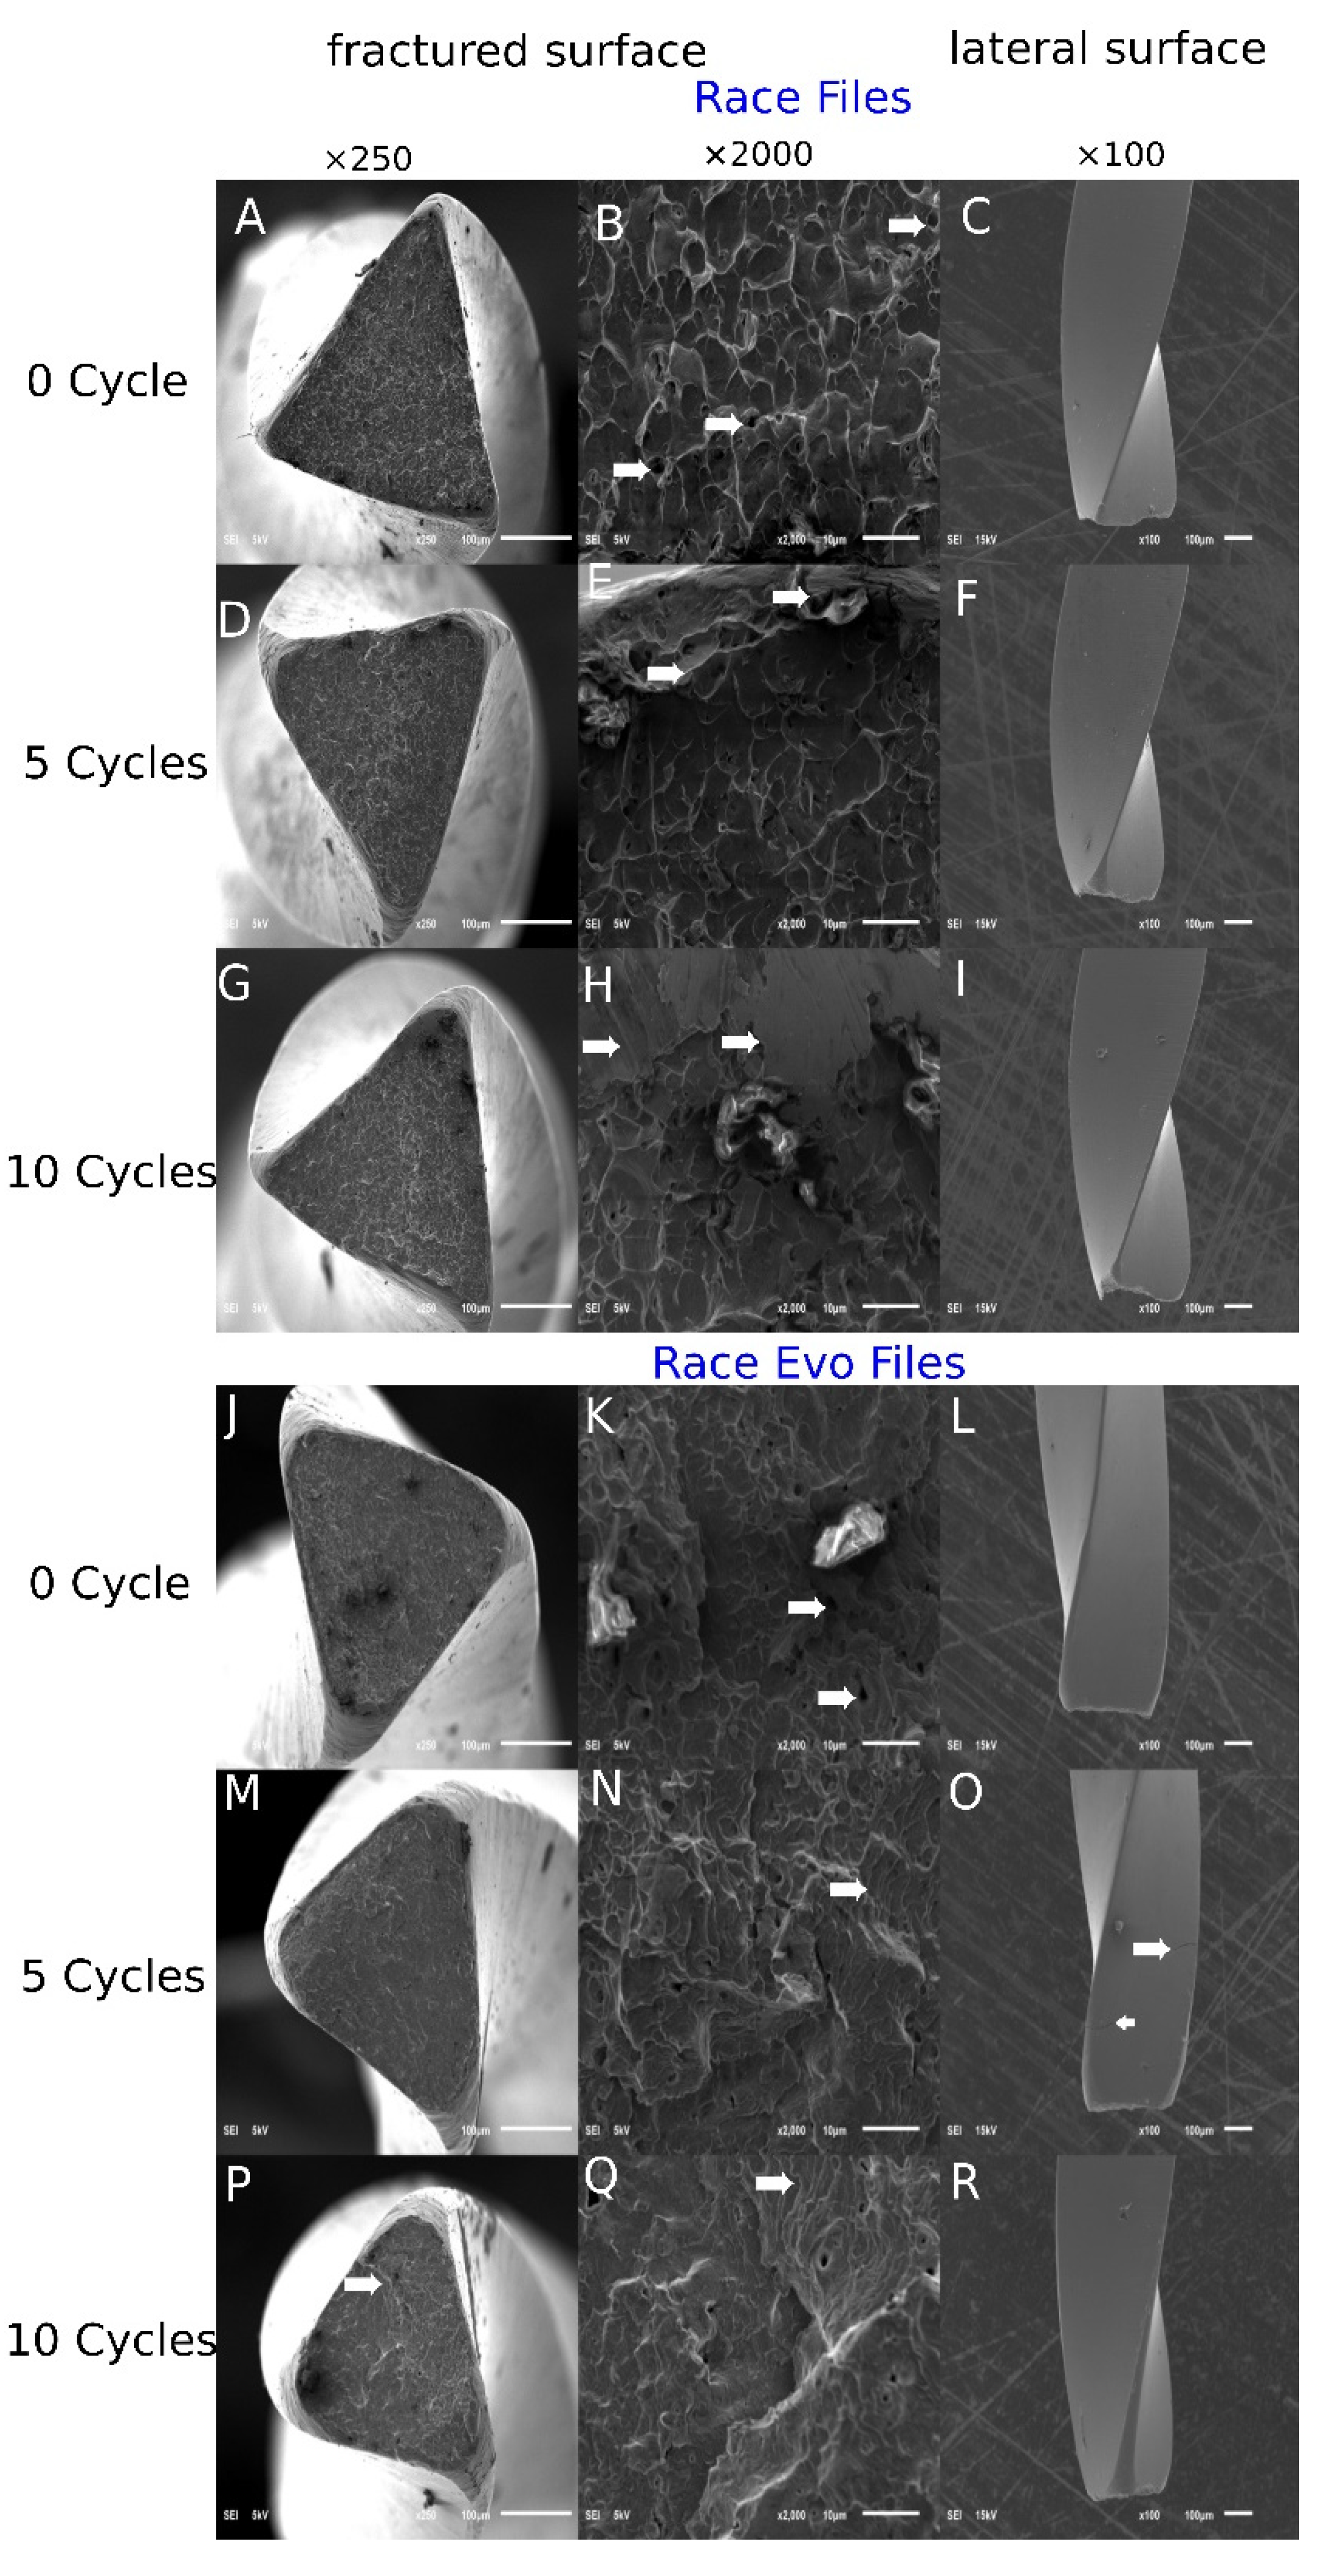

A scanning electron microscope (SEM; JSM-7001F, JEOL, Tokyo, Japan) was used to inspect the fractured instruments and evaluate the topographical characteristics of the fractured surfaces. Photomicrographs of the fractured surfaces were taken at 250× and 2000× magnification, in addition to photomicrographs of the lateral surface at 100× magnification.

The SEM photomicrographs can be seen in Figure 4. The images show fractured surfaces pre-autoclaving and then after 5 and 10 cycles. Arrows point to the distinct features on these fracture surfaces.

Through SEM, fractured surfaces tend to exhibit various textures that reflect the different loads and failure types. Failure as a result of flexural fatigue is usually characterized by linear striations perpendicular to the direction of the tensile stress and areas of crack initiation, while torsional fracture is associated with plastic deformation and dimpling patterns [28]. Race Evo files showed distinct striations typical of flexural fatigue radiating from an initiation point followed by dimpling, which is characteristic of ductile failure [29]. Features consistent with ductile and microvoid coalescence failure were seen on the fractured surfaces of both types of files [30].

Figure 4. Scanning electron microscope (SEM) images of the fractured surfaces (AI): Race files, (JR): Race Evo files) under low magnification (×250) and high magnification (×2000) pre-autoclaving, then after 5 and 10 autoclaving cycles. White arrows in (B) Dimple features characteristic of ductile failure; (E) Microvoids; (H,O) Crack initiation; (K,N,Q) Striation lines (fatigue failure).